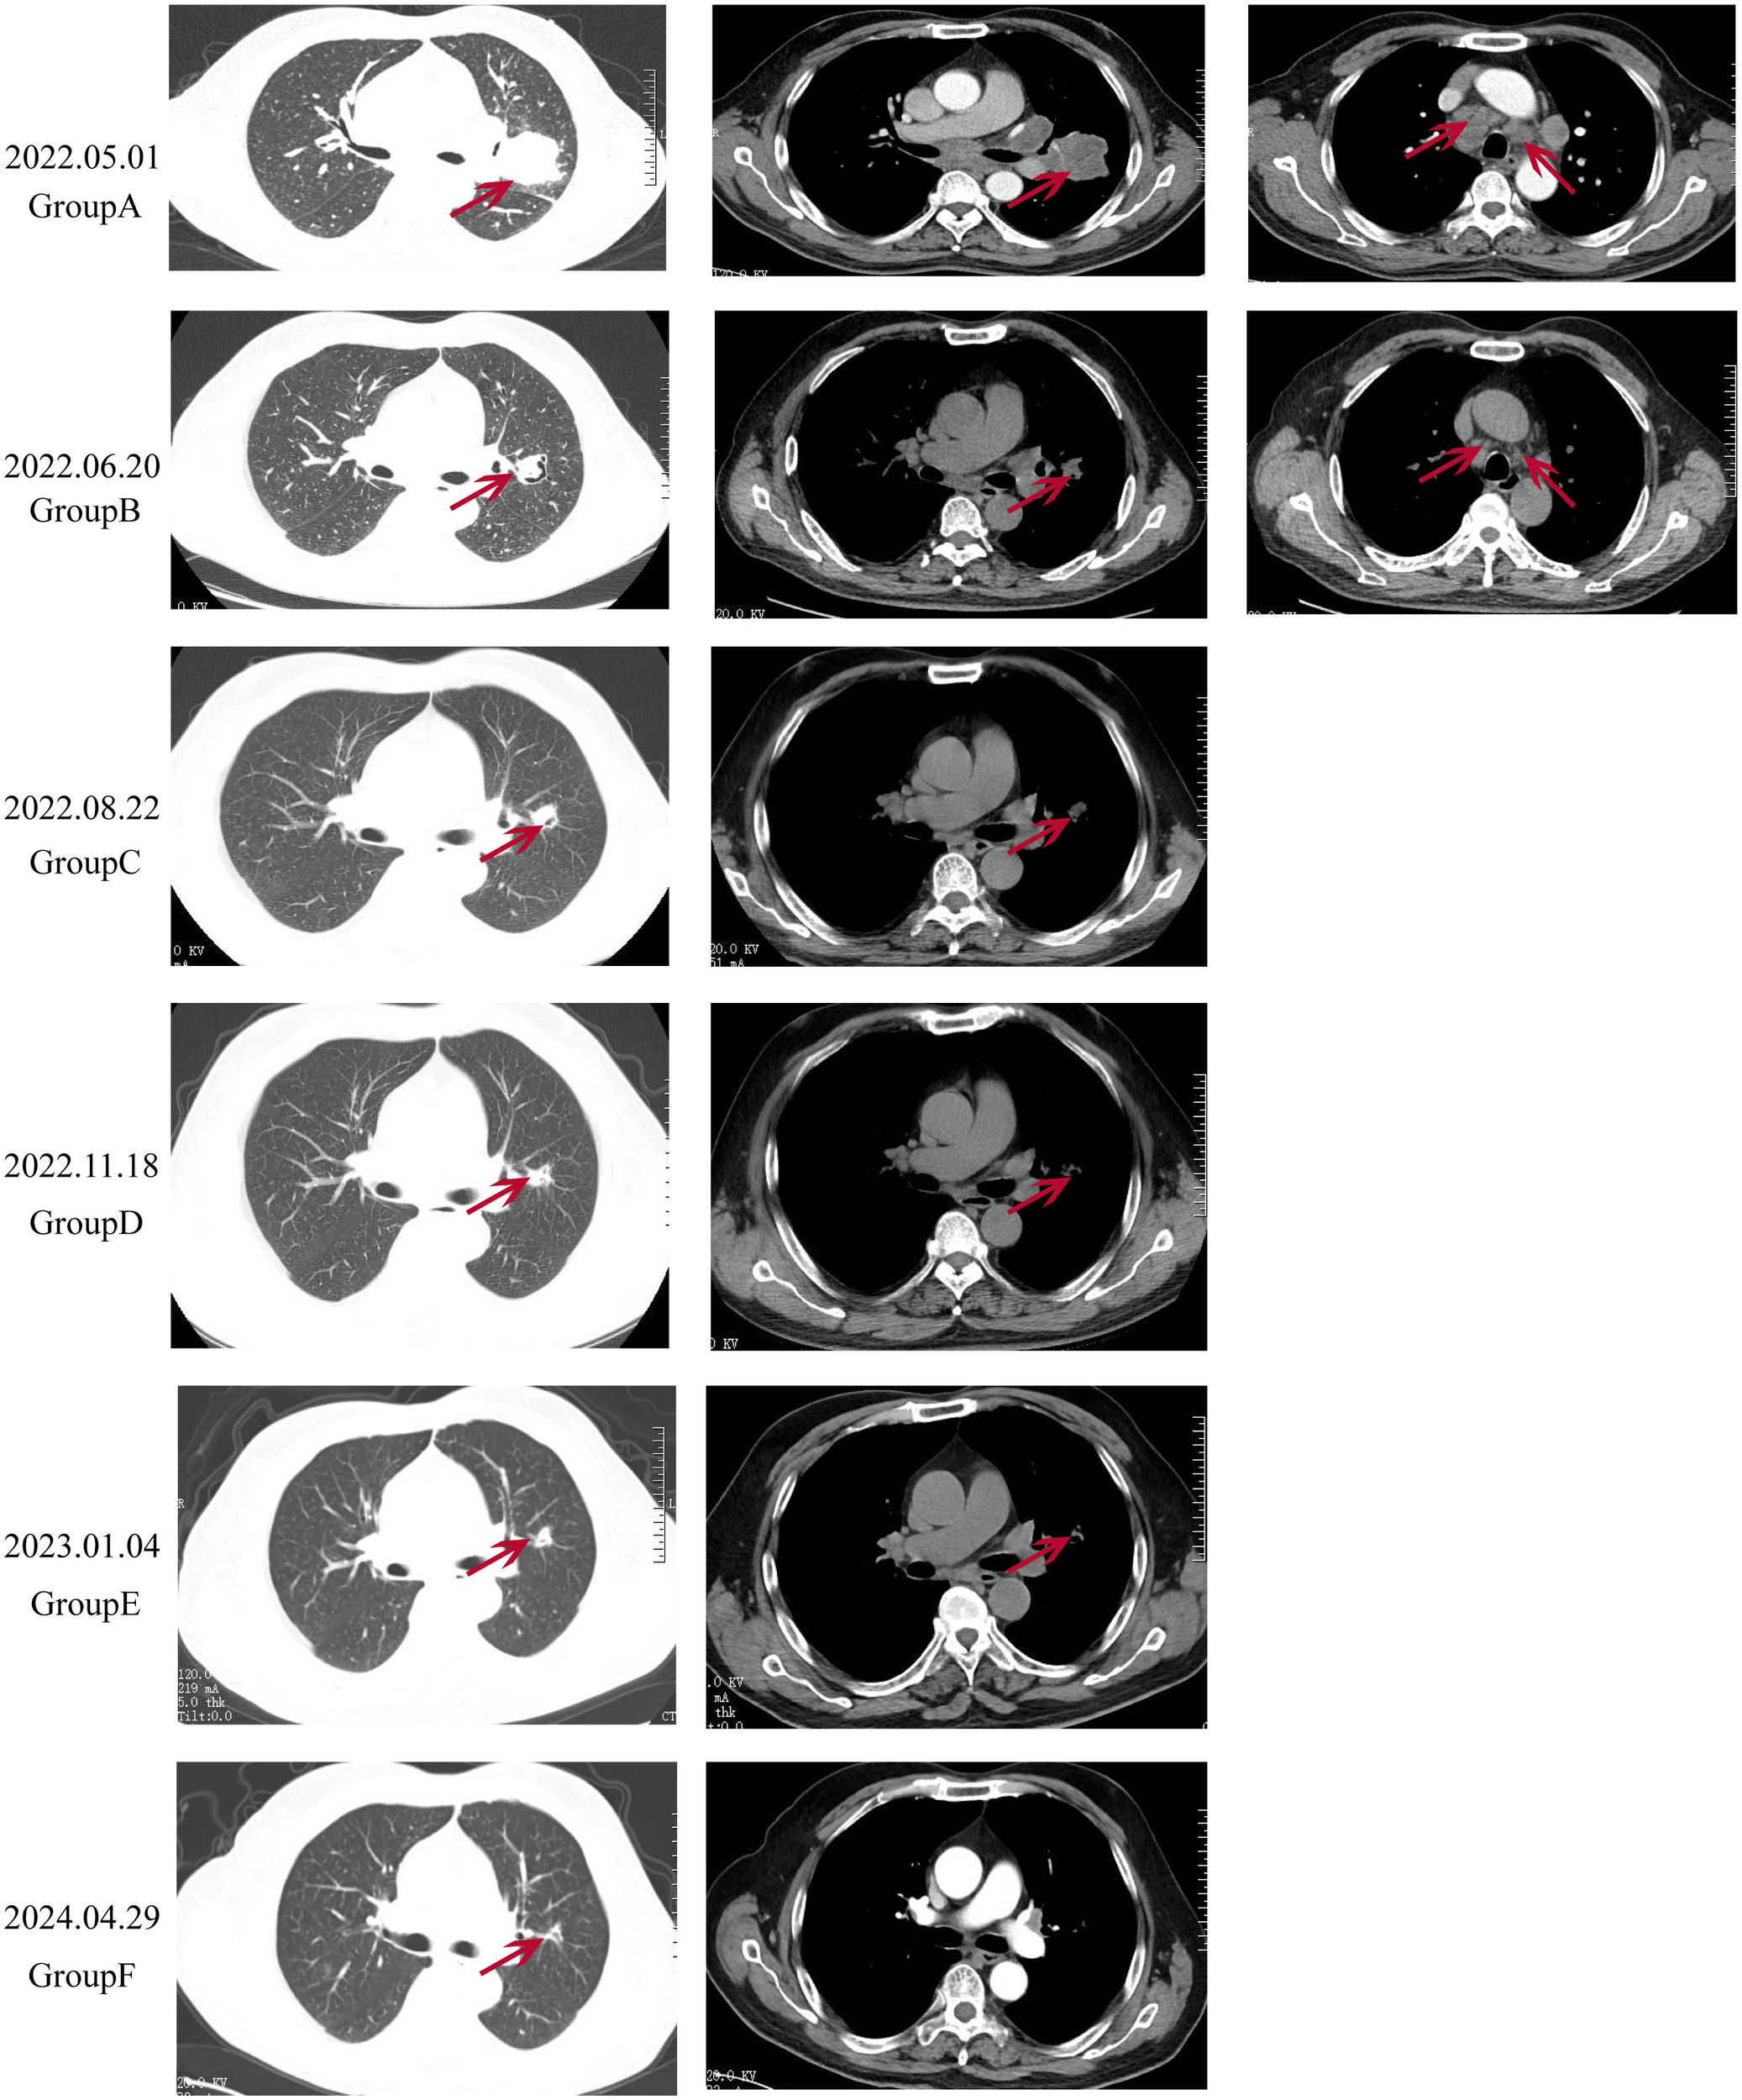

On April 22, 2022, a 67-year-old Chinese male presented with intermittent coughing for over 10 days underwent a chest X-ray at a local health clinic, revealing a lesion in the left lung. A subsequent chest computed tomography (CT) scan at a county-level hospital confirmed the presence of the lesion. The patient was then admitted to the First Affiliated Hospital of Henan Polytechnic University, where an enhanced chest CT scan showed an irregular soft tissue mass in the left lung with heterogeneous enhancement, measuring approximately 49mm x 50mm x 55mm. Multiple moderately enhanced nodular soft tissue density shadows were observed in the mediastinum, with some showing fusion (Figure 1A). The biomarker cytokeratin-19 fragment (CYFRA21-1) was elevated to 41.12 ng/ml (normal reference range <2.37 ng/ml). In adddition, the levels of biomarkers such as neuron-specific enolase (NSE) 、squamous cell carcinoma(SCC)、progastrin-releasing peptide(PROGRP)、carbohydrate antigen 242(CA24-4)、and carcinoembryonic antigen (CEA) were within the normal range throughout the disease and treatment course of the patients. The patient’s medical history included over 10 years of hypertension, a past case of hyperthyroidism which had been cured, and a 40-year smoking history of 20 cigarettes per day, with no family history of lung cancer.

Figure 1

Radiological changes in the patient’s lung before and after treatment. (A): Pre-treatment imaging showing a pulmonary mass measured approximately 49x50x55mm in size, with multiple enlarged and partially fused lymph nodes. (B): After 2 cycles of treatment, the tumor size reduced to approximately 30x32x34 mm, and the mediastinal lymph nodes significantly decreased in size. (C, D): Throughout the treatment, the lung tumor continued to shrink, and the mediastinal lymph nodes continues to decrease in size, with no mediastinal lymph nodes visible in (E). (F): During treatment, the tumor size was approximately 12x18x15 mm, with no significant enlargement of the mediastinal lymph nodes.

Due to the patient’s symptoms of headache and nausea, priority was given to whole-brain radiotherapy (WBRT) at a dose of 40Gy/23f and a local lesion dose of 50Gy/23f, over 23 sessions. High-throughput sequencing of lung tissue specimens was performed to evaluate genes associated with lung cancer, revealing a TP53 exon 4 c.313G mutation. PD-L1 expression (TPS) was 75%. Based on the guidelines from NMPA, NCCN, and ASCO, and a review of public databases, the patient was subsequently given Anlotinib at 12mg daily, administered for 2 weeks and 1-week off, constituting a 3-week (21 days) cycle. This was combined with Penpulimab injection at 200mg, administered every 3 weeks (21 days), as a first-line treatment regimen. Excitingly, after two cycles of combined treatment, a follow-up chest CT scan showed a significant reduction in the size of the tumor in the left upper lobe of the lung (30x32x34mm) and the mediastinal lymph nodes (Figure 1B). A follow-up enhanced brain MRI indicated that the abnormal signals in the right frontal-parietal lobe, left parietal lobe, left thalamus, and right cerebellar hemisphere appeared as spot-like and ring-like enhancements with clear boundaries. The brain metastases had significantly reduced in size, with the largest lesion in the right frontal lobe now measuring approximately 7mm in its longest diameter (Figure 3B). The patient’s clinical symptoms of brain metastases were remarkadly relieved, and the quality of life improved significantly.

Two months later, a follow-up examination showed that the tumor had shrunk to 21x29x22mm, and the mediastinal lymph nodes had also significantly reduced in size (Figure 1C). Subsequent bi-monthly chest CT scans showed continued tumor shrinkage. By November 18, 2022, a follow-up chest CT scan showed that the tumor had significantly reduced to 12x19x17mm, with no significant enlargement of the mediastinal lymph nodes (Figure 1D). Follow-up enhanced brain MRI indicated that the metastases in the left parietal lobe, left thalamus, and right cerebellar hemisphere had disappeared, with the largest lesion in the right frontal lobe remaining at approximately 7mm (Figure 3C). According to the RECIST 1.1 criteria, the patient’s condition was classified as partial response (PR).

During follow-up chest CT scans. the tumor size remained stable, and on January 4, 2023, a chest CT scan showed the tumor remained at 12x19x17mm, with no significant enlargement of the mediastinal lymph nodes (Figure 1E). On April 29, 2024, a follow-up enhanced chest CT scan showed the tumor size was 12x18x15mm, with no significant enlargement of the mediastinal lymph nodes (Figure 1F). The CYFRA21-1 level had decreased to 2.61 ng/ml (normal range <2.37 ng/ml). According to RECIST 1.1 criteria, the patient’s condition was classified as stable disease (SD). The patient’s CYFRA21-1 level has stabilized between 2 and 3 ng/ml (Figure 4). Considering the sustained disease stability and the patient’s good tolerance, the Penpulimab treatment was lasted for two years and has now ended. The patient continues with maintenance therapy using Anlotinib monotherapy and is currently under regular monitoring and ongoing treatment.